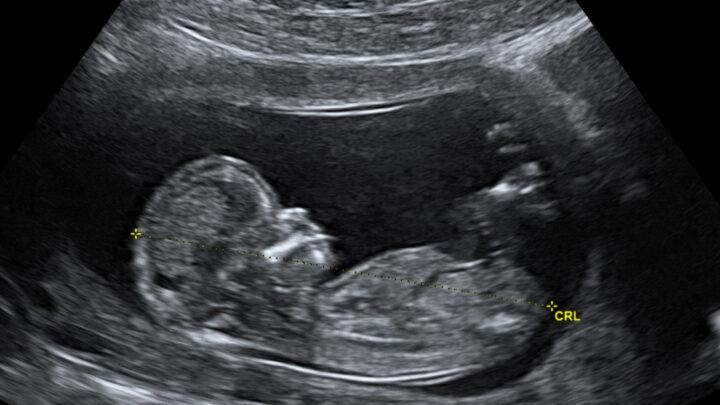

Ultrassonografia

Ultrassonografia Pélvica

Se você passou por períodos dolorosos, sangramento vaginal incomum, dor pélvica crônica ou dificuldade em engravidar, pode recomendar uma ultrassonografia…